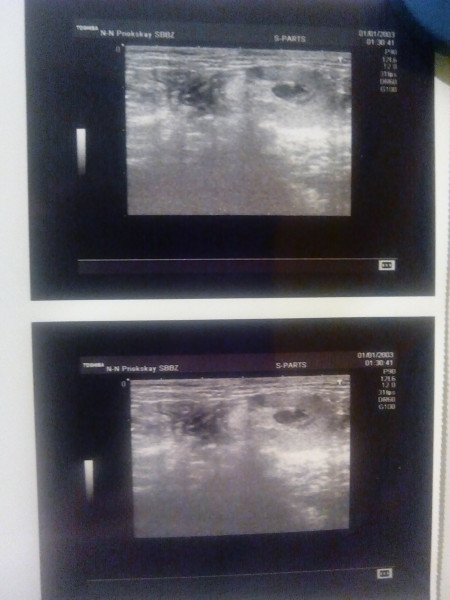

В клинике Скрипу сделали узи мочевого пузыря: диагностирован наполненный мочевой пузырь и много песка в моче. Врач сказала, что произошла закупорка уретры. Нужна катетеризация. Делали без седирования чтобы не нагружать почки. Уретра была плотно забита песком. В результате нескольких попыток вставить трубочку удалось сцедить мочу и вышел сгусток песка. Перед поездкой в клинику был куплен котэрвин о чем я сказала врачу. Врач назначила Скрипу лечение и котэрвин по умолчанию. Из сцеженной мочи взяли пробу и отвезли на анализ.

Котейка пережил в тот день огромный стресс. Он очень тяжело относится к транспортировке и + болевые ощущения. Сегодня уже четвертый день Скрипка на уколах. Ляжечки все болят(, ребенок грустный и напуганный. Мочится два раза в сутки сам.

В клинике стоял вопрос о том оставить ли катетер и подшить или пока погодить. Решено было дать ему возможность просикаться самому в противном случае снова экстренно в клинику на катетеризацию.